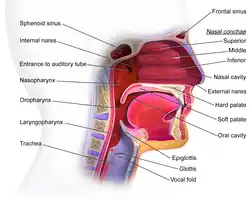

The oropharynx, at the back of the mouth, forms a circle and includes the base of the tongue (posterior third) below, the tonsils on each side, and the soft palate above, together with the walls of the pharynx, including the anterior epiglottis, epiglottic valleculae and branchial cleft at its base. The oropharynx is one of three divisions of the interior of the pharynx based on their relation to adjacent structures (nasal pharynx (nasopharynx), oral pharynx (oropharynx) and laryngeal pharynx (laryngopharynx – also referred to as the hypopharynx), from top to bottom). The pharynx is a semicircular fibromuscular tube joining the nasal cavities above to the larynx (voice box) and oesophagus (gullet), below, where the larynx is situated in front of the oesophagus.[31]

The oropharynx lies between the mouth (oral cavity) in the front and the laryngopharynx below, which separates it from the larynx. The upper limit of the oropharynx is marked by the soft palate and its lower limit by the epiglottis and root of the tongue. The oropharynx communicates with the mouth, in front through what is known as the oropharyngeal isthmus, or isthmus of the fauces. The isthmus (i.e., connection) is formed above by the soft palate, below by the posterior third of the tongue, and at the sides by the palatoglossal arches. The posterior third of the tongue or tongue base contains numerous follicles of lymphatic tissue that form the lingual tonsils. Adjacent to the tongue base, the lingual surface of the epiglottis, which curves forward, is attached to the tongue by median and lateral glossoepiglottic folds. The folds form small troughs known as the epiglottic valleculae. The lateral walls are marked by two vertical pillars on each side, the pillars of the fauces, or palatoglossal arches. More properly they are separately named the palatoglossal arch anteriorly and the palatopharyngeal arch posteriorly. The anterior arch is named from the palatoglossal muscle within, running from the soft palate to the tongue (glossus), while the posterior arch similarly contains the palatopharyngeal muscle running from the soft palate to the lateral pharynx. Between the arches lies a triangular space, the tonsillar fossa in which lies the palatine tonsil, another lymphoid organ. [32]

The external pharyngeal walls, consisting of the four constrictor muscles, form part of the mechanism of swallowing. The microscopic anatomy is composed of four layers, from the lumen outwards, the mucosa, submucosa, muscles, and the fibrosa, or fibrous layer. The mucosa consists of stratified squamous epithelium, which is generally non-keratinised, except when exposed to chronic irritants such as tobacco smoke. The submucosa contains aggregates of lymphoid tissue.[32][33]